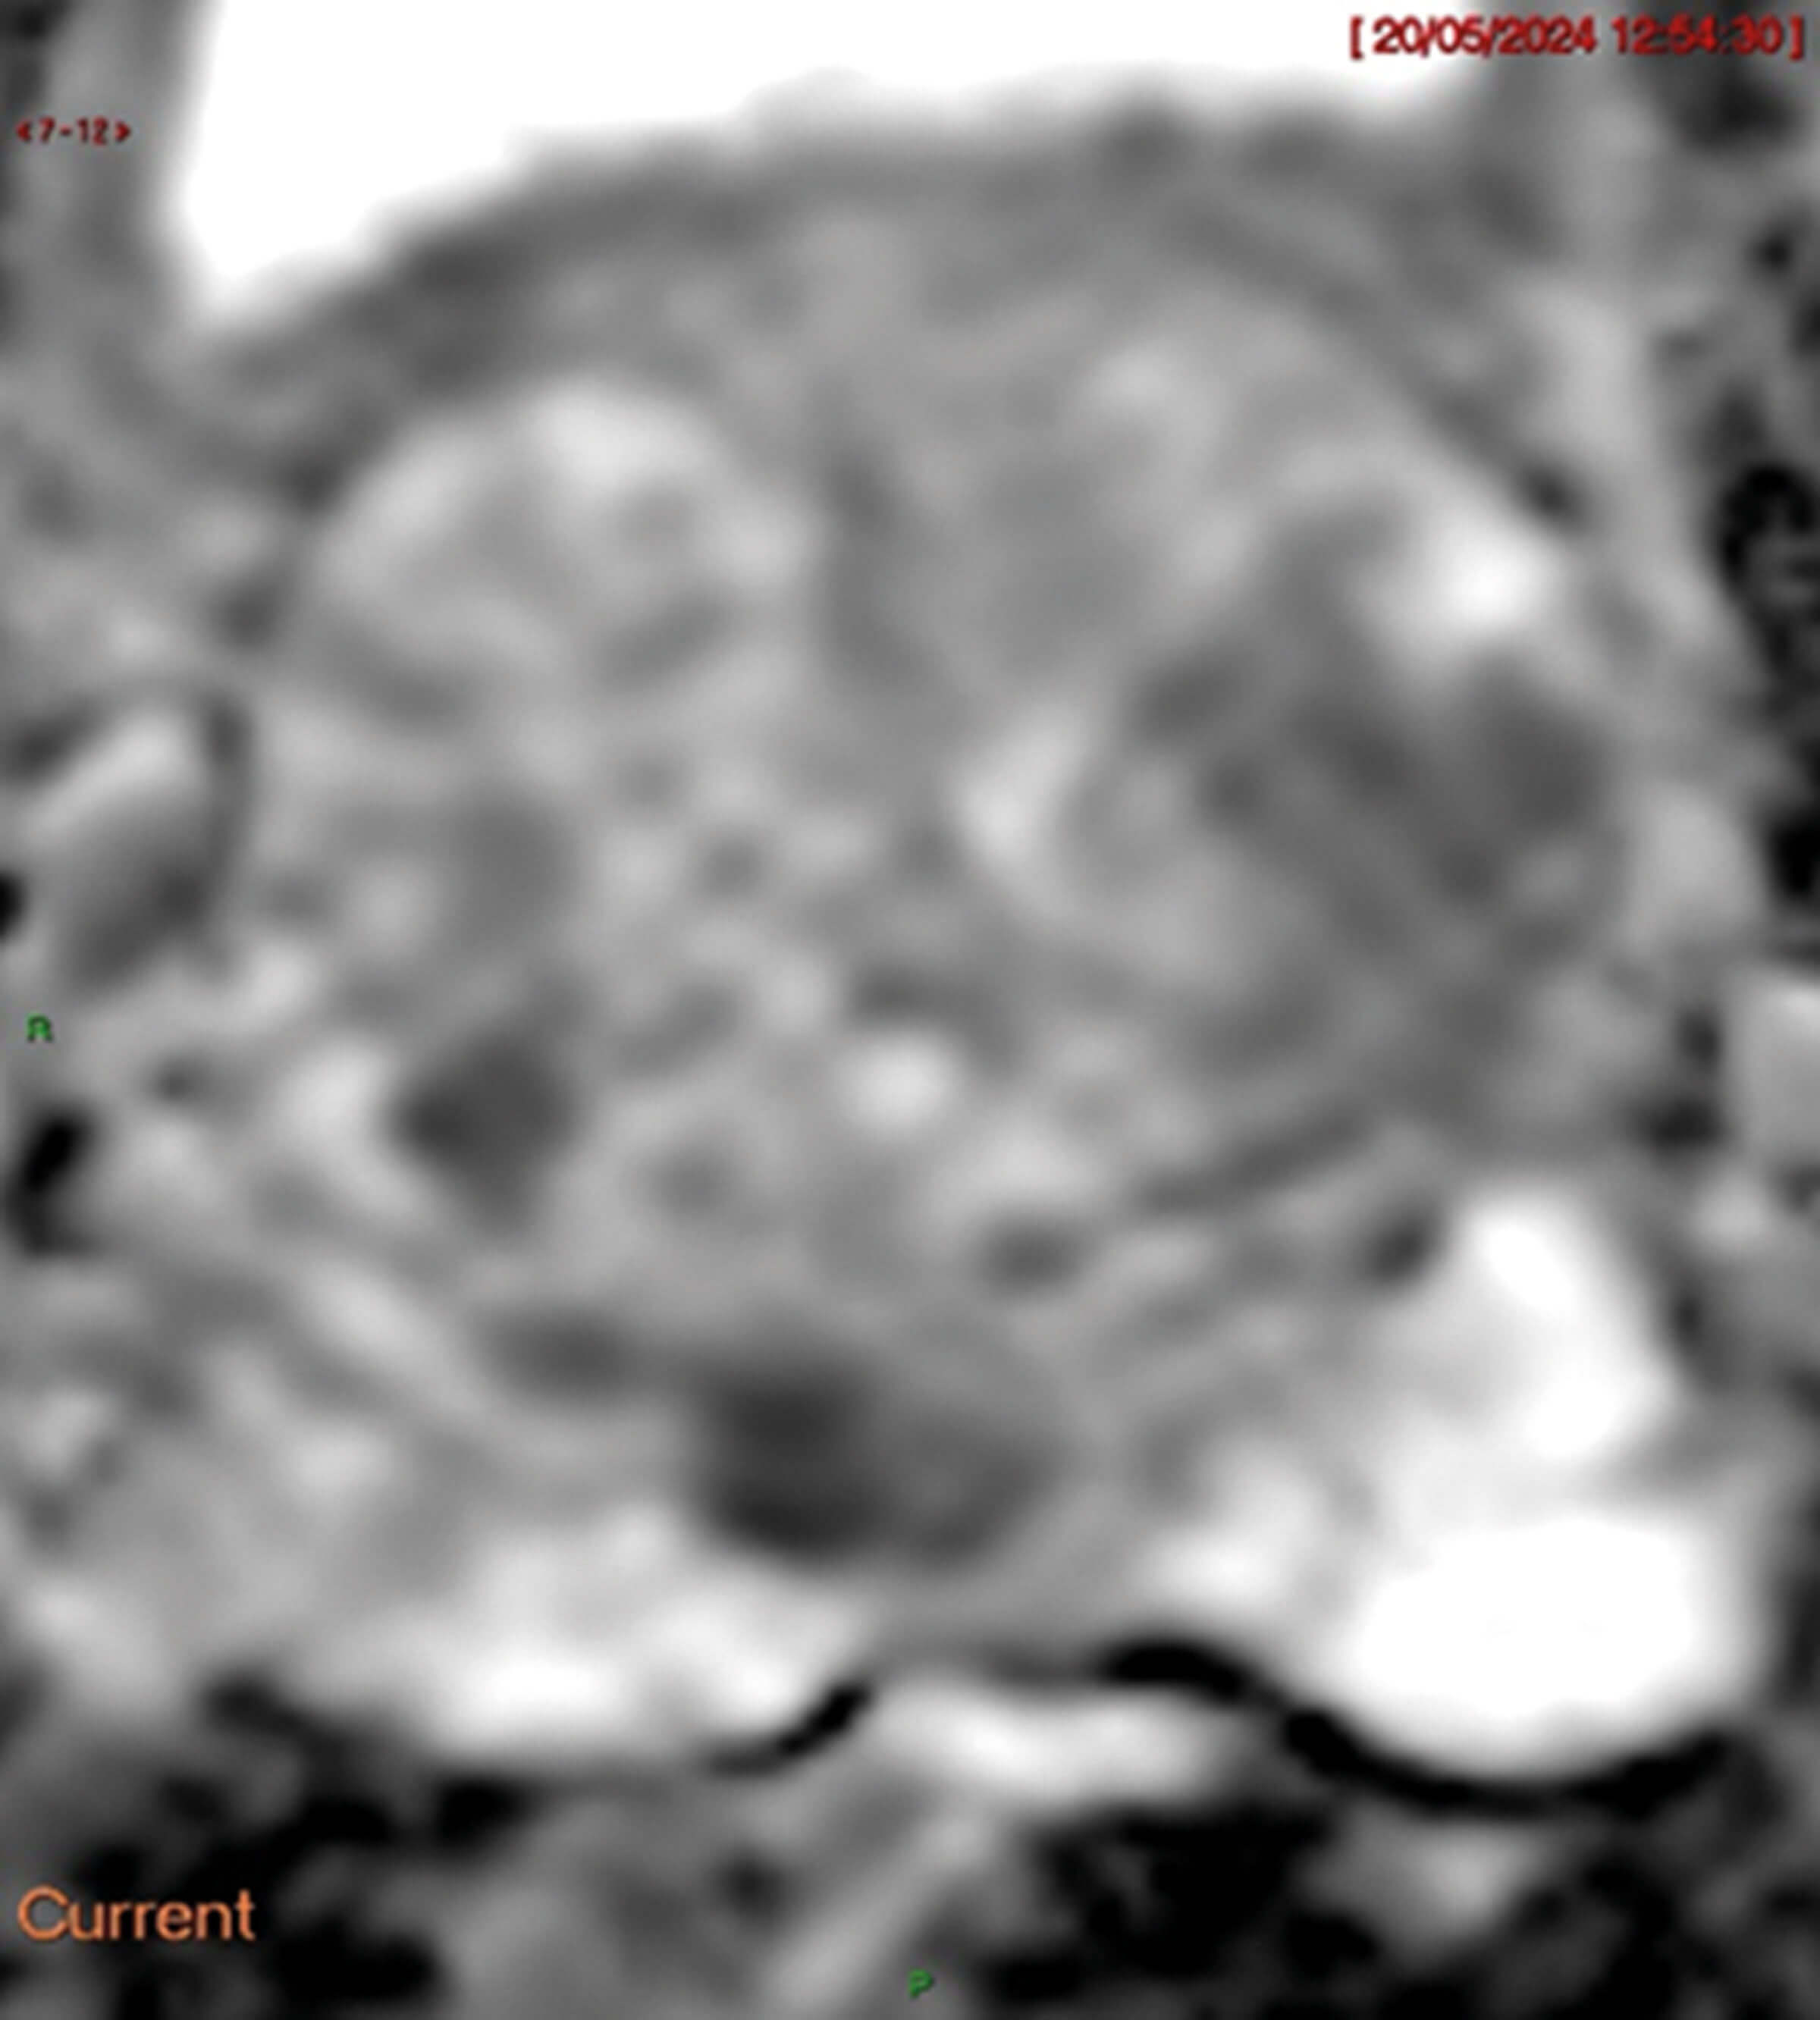

Figure 3.

- Figures 2-4 are the different MRI sequences. What sequences are they and what do they represent?

The b-value (s/mm2) is a measure of the different gradients of diffusion weighting applied and by applying different pulses and calculating diffusion gradients aids in tumour detection. Different b-values are required to calculate the apparent diffusion coefficient (ADC, Figure 3), and higher b-values increase sensitivity to restricted diffusion, aiding in tumour detection. ADC is calculated by a specific formula.

Cancer typically appears bright on DWI (Figure 2) and darker on ADC (Figure 3) and radiologists compare sequences to check if they correlate.